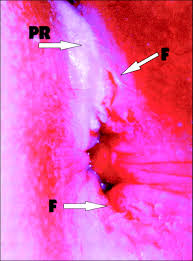

Thought it make a good cover. This will be the cover of my next issue of my zine broken hymen. Hymen with a generally crescent shaped opening. He broke into the gym and charged people too much for basketball games. About unbroken unbroken summary character list glossary themes quotes analysis symbols, allegory and motifs metaphors and similes irony imagery literary elements essay questions. If your child has broken his leg, do not try to move him yourself. An operation does exist and is performed in some countries (sometimes illegally) that can cut open the fragments of a broken hymen and sew them back together to form a likeness of an unbroken hymen. A broken bone in a child is different from one in an adult, because young bones are more flexible and have a thicker covering extreme cold can cause injury to the delicate skin of babies and toddlers, so do not use ice with children this young.